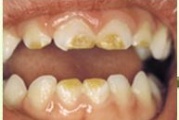

Tetratsükliini liigtarbimise tõttu värvunud hambad

Fluoroos

Fluoroosi